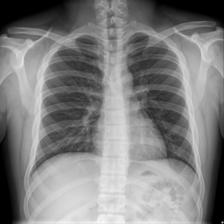

To pre-train a high-performance X-ray foundation model, the first thing we need to do is the collection of large-scale X-ray images. Therefore, a large-scale and high-resolution dataset that contains X-ray medical images is collected for the pre-training. Some representative samples are visualized in Fig. 3.